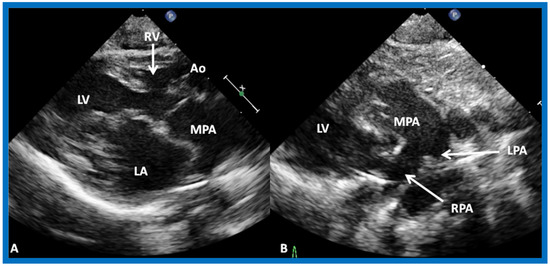

(A) Selected video frame from precordial long axis views of a neonate with tricuspid atresia and transposition of the great arteries demonstrating the left atrium (LA), left ventricle (LV), a very small right ventricle (RV) and a moderate sized ventricular septal defect (not marked). The vessel coming off of the LV is traced in (B) and shown to bifurcate into left (LPA) and right (RPA) pulmonary arteries, confirming that this is the main pulmonary artery (MPA). Ao, Aorta. Reproduced from Rao P.S. [39].

Figure 22.

Selected video frame from precordial long axis view with color flow mapping of another neonate with tricuspid atresia and transposition of the great arteries illustrates the left atrium (LA), left ventricle (LV), a small right ventricle (RV) and a moderate sized ventricular septal defect (VSD). The vessel coming off of the LV bifurcates into left (LPA) and right (RPA) pulmonary arteries. Reproduced from Rao P.S. [39].